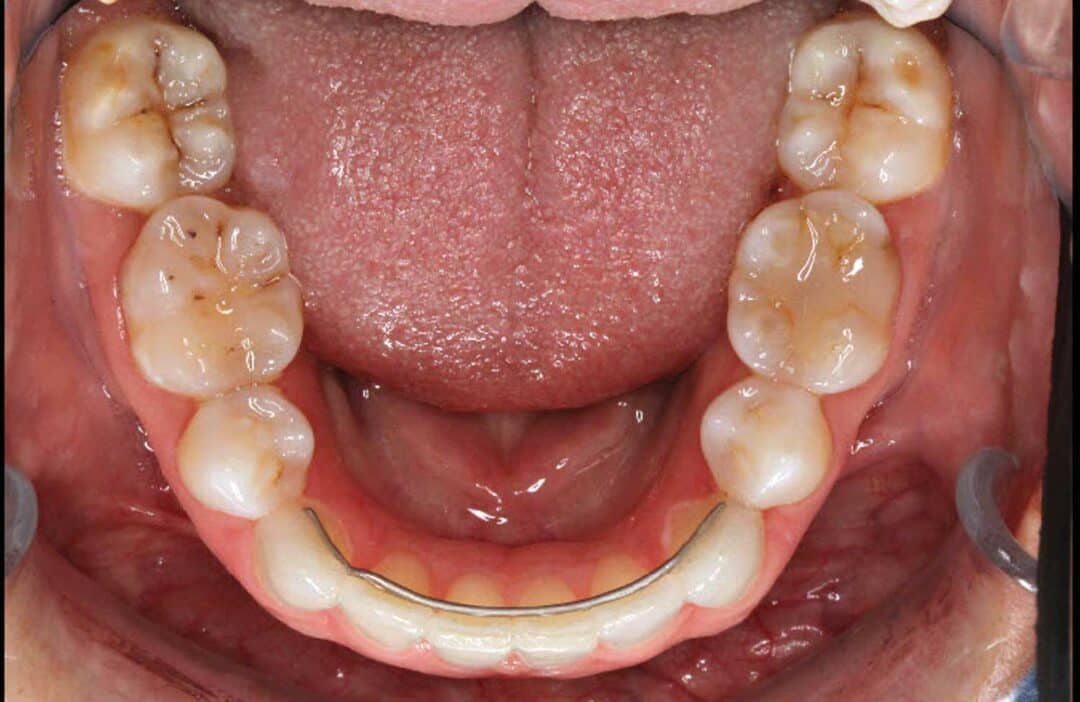

From www.researchgate.net

Facial and intraoral photographs of relapse after 3year posttreatment What Is Orthodontic Relapse When this change occurs shortly after treatment, the. Orthodontic relapse is defined as the return of the treated teeth to the initial position, with partial or total recurrence. Orthodontic relapse refers to the gradual shifting of teeth after completing orthodontic treatment, which can ultimately. Orthodontic relapse refers to the tendency of teeth to move back towards their original positions after.. What Is Orthodontic Relapse.

From www.jwfo.org

Comparing orthodontic relapse of mandibular anterior teeth with What Is Orthodontic Relapse An orthodontic relapse occurs when your teeth shift out of position after treatment. Orthodontic relapse refers to the tendency of teeth to move back towards their original positions after. The teeth have a tendency to move back to their original position even after a dentist declares the orthodontic. Orthodontic relapse is defined as the return of the treated teeth to. What Is Orthodontic Relapse.